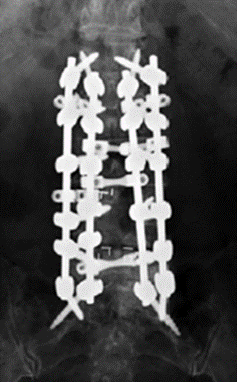

图36 多棒固定向两棒固定的过渡

图37 半坚强固定